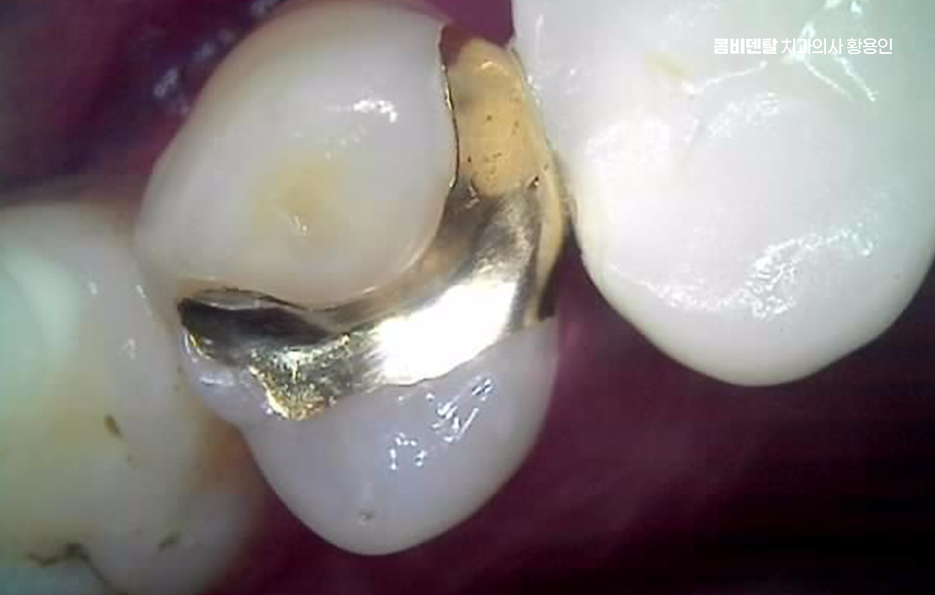

지금도 입 안에 아말감이 남아 있는 분들이 많고, 오랜 기간 큰 문제 없이 사용한 경우도 있지만 아말감은 금속 재료이기 때문에 시간이 지나면서 치아와는 다른 방식으로 변화하며 열에 의한 팽창과 수축이 반복되면서 치아와 아말감 사이에 미세한 틈이 생길 수 있고, 그 틈으로 세균이 침투하면서 안쪽에서 충치가 다시 진행되는 경우가 있어요.

문제는 이런 2차 충치가 겉으로 잘 보이지 않는다는 점이며 겉에서 보기에는 아말감이 단단히 붙어 있는 것처럼 보여도, 그 아래에서는 치아가 이미 많이 약해져 있는 경우도 있었어요.

이런 상태에서는 어느 날 갑자기 치아가 깨지거나, 씹을 때 통증이 생기면서 문제를 인식하게 되는 경우가 많아서 아말감이 떨어지기 전까지는 괜찮다라고 생각하는 것은 위험할 수 있었어요.

아말감 뿐 아니라 오래된 보철물도 비슷한 문제를 안고 있는데 크라운이나 인레이 같은 보철물은 치아를 보호하는 역할을 하지만, 영구적인 것은 아니며 시간이 지나면서 보철물 가장자리와 잇몸 경계 부위에 미세한 틈이 생길 수 있고, 그 안쪽으로 충치가 진행될 수 있으며 특히 오래된 보철물은 제작 당시의 기술이나 재료 특성 때문에 지금 기준으로 보면 밀착도가 떨어지는 경우도 있어요.

아말감을 교체하는 경우에는 단순히 아말감을 제거하고 다른 재료로 채우는 것으로 끝나지 않는 경우도 많은데 제거 과정에서 이미 약해진 치아 구조가 드러나면서, 생각보다 손상 범위가 큰 경우도 있었어요.